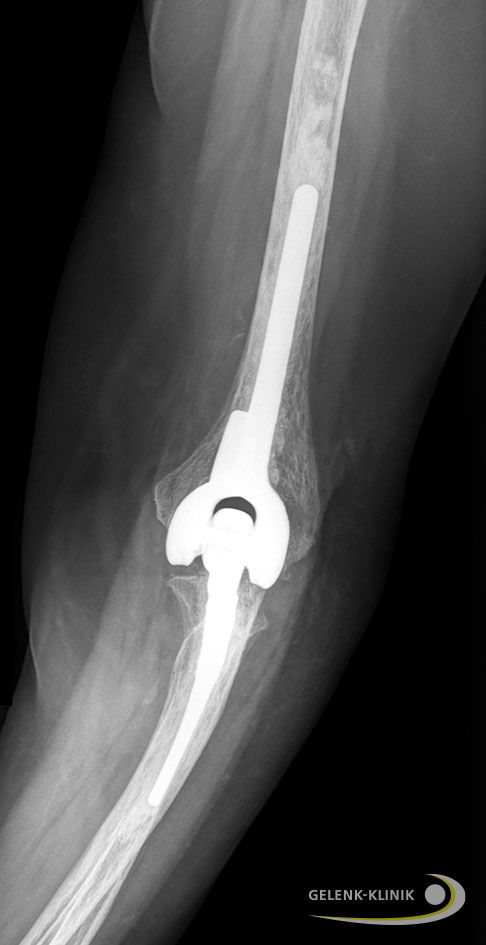

Seitliche Röntgenaufnahme des Ellenbogengelenks nach Implantation einer Ellenbogenprothese in den Knochenschaft des Oberarms (Humerus) und der Elle (Ulna). Alle Komponenten des Ersatzgelenks sind miteinander verbunden (gekoppelte Ellenbogenprothese) und arbeiten wie ein Scharnier. Der Kopplungsmechanismus übernimmt die stabilisierende Funktion des Bandapparats und gewährleistet eine gute Gelenkstabilität. © Gelenk-Klinik

Gekoppelte Ellenbogenprothese

Bei der gekoppelten Ellenbogenprothese sind alle Komponenten des Ersatzgelenks miteinander verbunden. Die Prothese arbeitet wie ein Scharnier. Der Kopplungsmechanismus übernimmt die stabilisierende Funktion des Bandapparats und gewährleistet eine gute Gelenkstabilität. Der Ellenbogenspezialist wählt dieses Modell vor allem bei fortgeschrittener Zerstörung des Gelenks, z.B. durch eine Rheuma-Erkrankung. Die Lockerungsrate der gekoppelten Ellenbogenprothese liegt etwas höher als bei ungekoppelten Prothesen. Verursacht wird eine mögliche vorzeitige Lockerung durch die stärkere Belastung der Prothesen-Knochen-Verbindung. Vor allem körperlich aktive Patienten, die ihr Ellenbogengelenk stark belasten, haben ein höheres Risiko für eine vorzeitige Prothesenlockerung.

Die Ellenbogenprothese besteht aus zwei Schenkeln aus hochwertigem Metall. Diese beiden Schenkel werden in den Schaftanteilen von Ober- und Unterarm fest verankert und ersetzen die Knochenanteile, die das natürliche Ellenbogengelenk formen. Sie sind durch ein Scharnier aus Metall und Kunststoff miteinander verbunden, das die Beugung des künstlichen Ellenbogengelenks ermöglicht. © Gelenk-Klinik